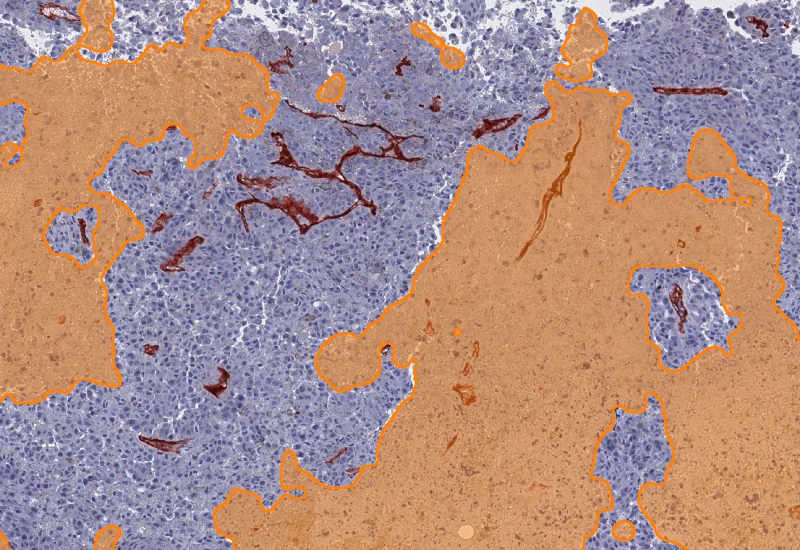

IHC Necrotic Tumor Angio

Segment tumor tissue into tumor, necrotic tissue, and blood vessels using an AI classifier, and quantify compartment areas, total vessel count, and vessel distribution across morphological entities.

The IHC Necrotic Tumor Angio App is able to segment tumor tissues into tumor, necrotic tissue and blood vessels using the AI Classifier. It outputs area of tumor, necrotic tissue and blood vessels as well as the number and percentage of blood vessels in total and within the two morphological entities.

Vessel detection

Necrotic tissue detection

Tumor detection

Combined detection